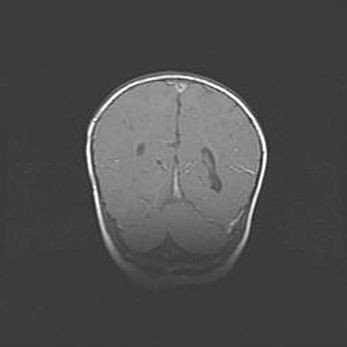

Наружная гидроцефалия с возможной атрофией височных областей.

Возраст: 28 дней

Вес: 3670 г

Пол: мужской

Окружность головы: 38 см

Срок гестации: 40 недель

Гидроцефалия головного мозга у новорожденных – это заболевание, которое характеризуется скоплением избыточного количества спинномозговой жидкости в желудочковой системе головного мозга в результате затруднения её перемещения от места выработки к месту поглощения в кровеносную систему или вследствие нарушения абсорбции. При открытой наружной форме гидроцефалии у новорожденных расширяются и переполняются субарахноидные пространства.

При нормотензивных  формах,  которые,  как  правило,  являются  следствием  перенесенных ишемических  повреждений  паренхимы  мозга,  возможно  сочетание микроцефалии  с нормотензивной гидроцефалией. В основе данных изменений лежит атрофия больших полушарий с преимущественной  локализацией  в  лобно-височных  областях.